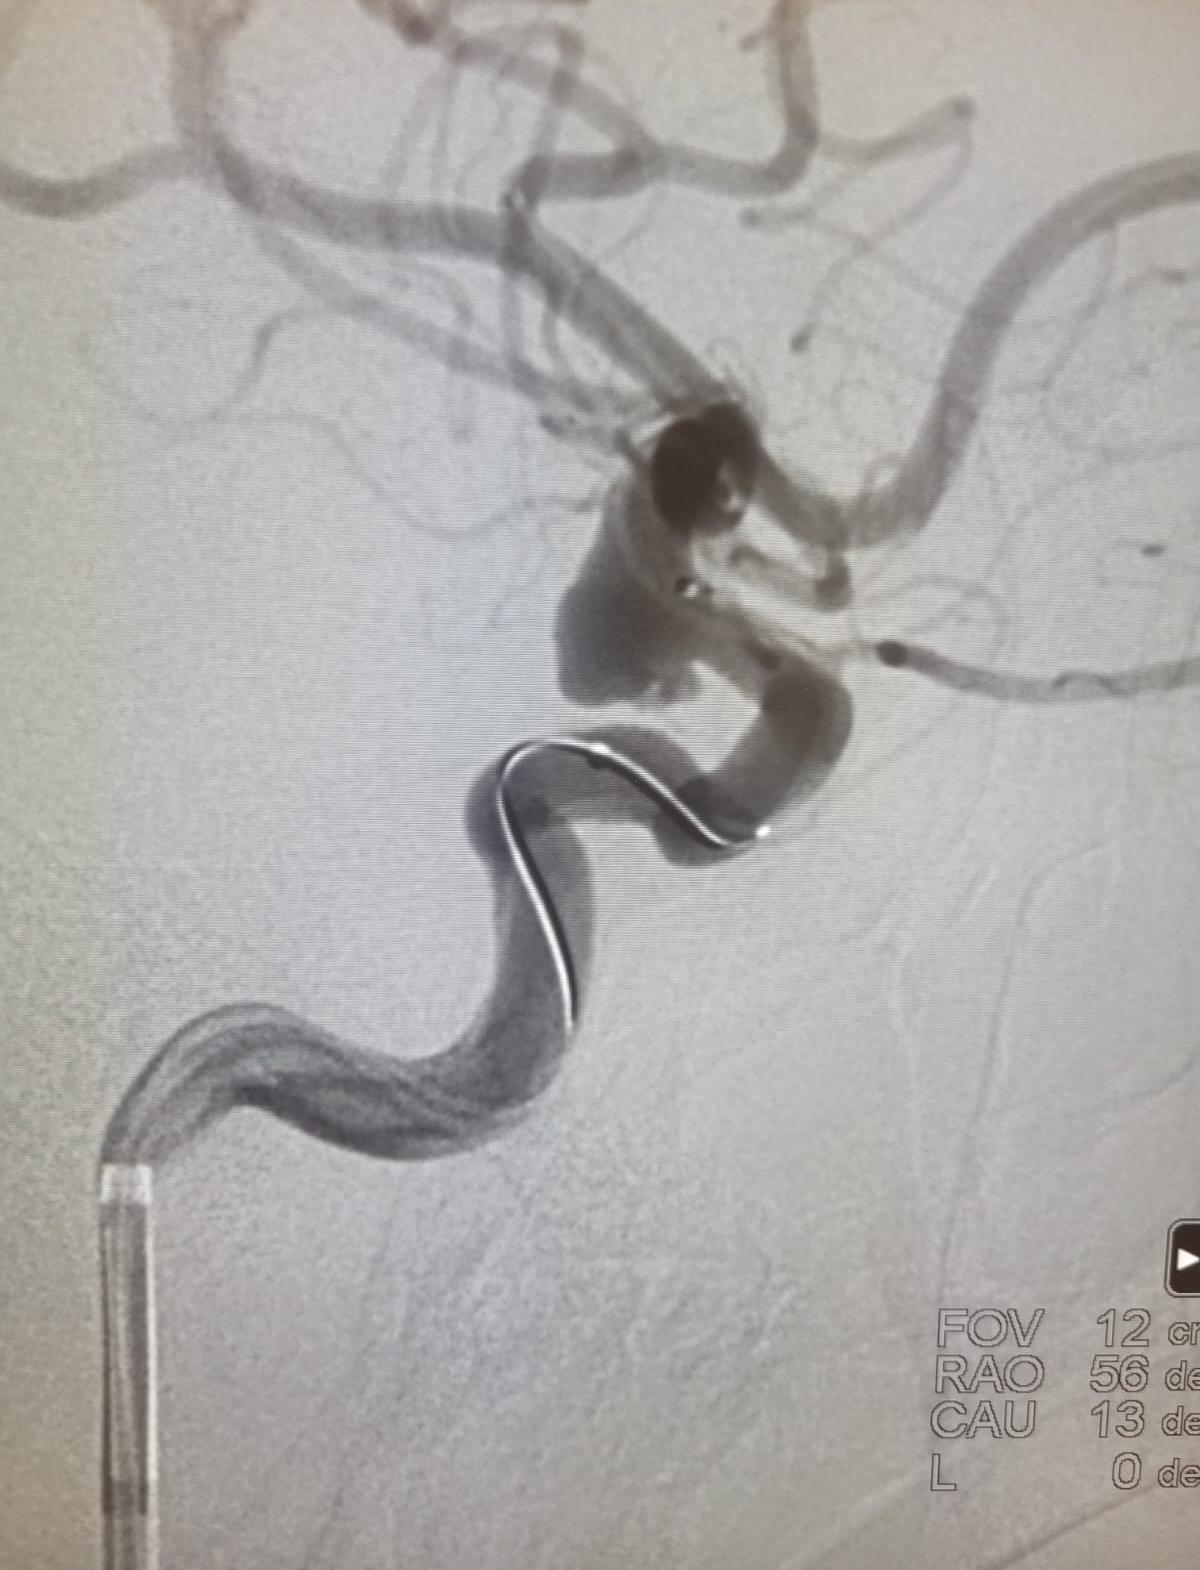

Консилиумом специалистов учреждения (нейрохирургов, акушеров-гинекологов, лучевых диагностов) было принято решение о дообследовании беременной. Результаты КТ-ангиографии выявили, что внутричерепное кровоизлияние обусловлено разрывом внутричерепной аневризмы коммуникантного сегмента правой внутренней сонной артерии. Иными словами, выпячивание стенки кровеносного сосуда просто прорвалось. Ситуация была критическая.

Характер аневризмы не оставлял докторам выбора — требовалась реконструкция пораженной артерии с помощью стента. Единственным адекватным методом лечения являлась внутрисосудистая окклюзия аневризмы (намеренная закупорка) спиралями со стент-ассистенцией. При этой процедуре необходимо вводить препараты, разжижающие кровь. Однако выполнение одномоментного родоразрешения и такой операции на фоне снижения свертывания крови представляло повышенную опасность ввиду высокого риска маточного кровотечения. Комплекс сложнейших задач встал перед мультидисциплинарной бригадой врачей центра.

Днем 31 декабря, в преддверии Нового года, бригада нейрохирургов в составе ведущего сосудистого нейрохирурга, заведующего нейрохирургическим отделением № 3 к.м.н. Андрея Евгеньевича Петрова и врача-нейрохирурга к.м.н. Аркадия Александровича Иванова в Перинатальном центре выполнила оперативное лечение разорвавшейся аневризмы.

Через прокол на руке ввели специальные микроспирали, которые закрыли разрыв аневризмы, и поставили стент, который не позволит ситуации повториться (имплантировали ассистирующий стент на фоне двойной дезагрегантной терапии).